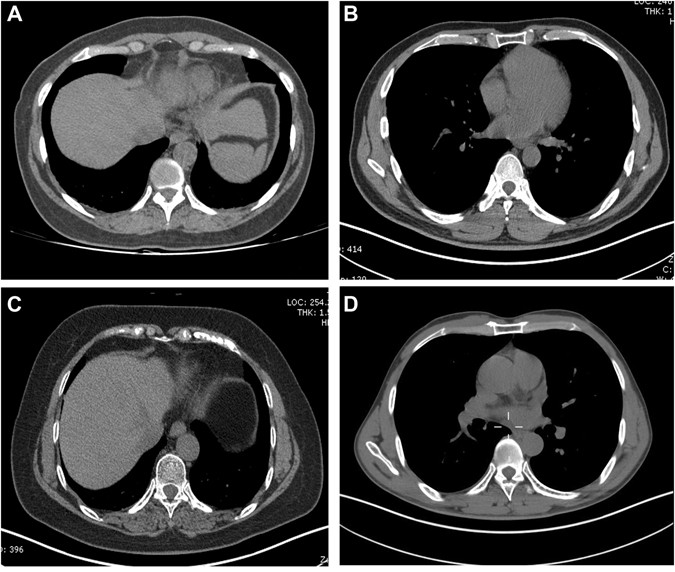

Calcification patterns of costal cartilage. Calcification patterns of costal cartilage were divided into the following types: (A) central, (B) peripheral, (C) mixed and (D) no calcification.